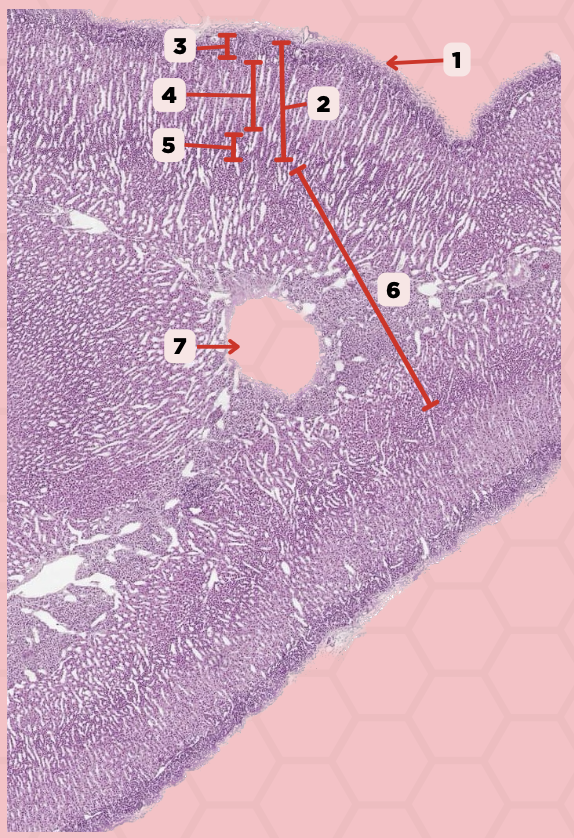

Pineal Body

Identify the specimen.

Capsule

Identify the structure labeled as 1.

Fenestrated Capillaries

What type of capillaries are embedded inside #1?

Pineal Body

Identify the specimen.

Lobule

Identify the structure labeled as 1.

#5 Pinealocytes (Chief Cells)

Which among these structures are modified neurons that are responsible for synthesizing melatonin?

#1 Interstitial Cells

Which among these are supporting cells that are morphologically similar to astrocytes?

Interstitial Cells

Identify the structure labeled as 1.

Clusters (Cords) of Cells

Identify the structure labeled as 2.

Capillaries

Identify the structure labeled as 3.

Lobule

Identify the structure labeled as 4.

Pinealocyte

Identify the structure labeled as 5.

True

True or False: These (#1) are extracellular/calcified bodies that increase with age.

Corpora Arenacea

Identify the structure labeled as 1.